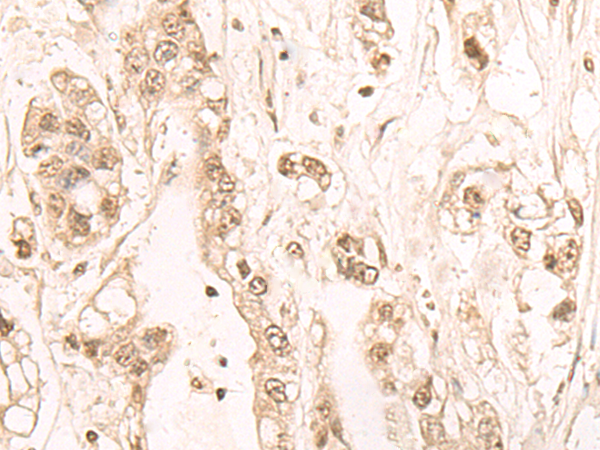

The image is immunohistochemistry of paraffin-embedded Human ovarian cancer tissue using P02776(FTSJ3 Antibody) at dilution 1/20. (Original magnification: ×200) |

The image is immunohistochemistry of paraffin-embedded Human gastric cancer tissue using P02776(FTSJ3 Antibody) at dilution 1/20. (Original magnification: ×200) |